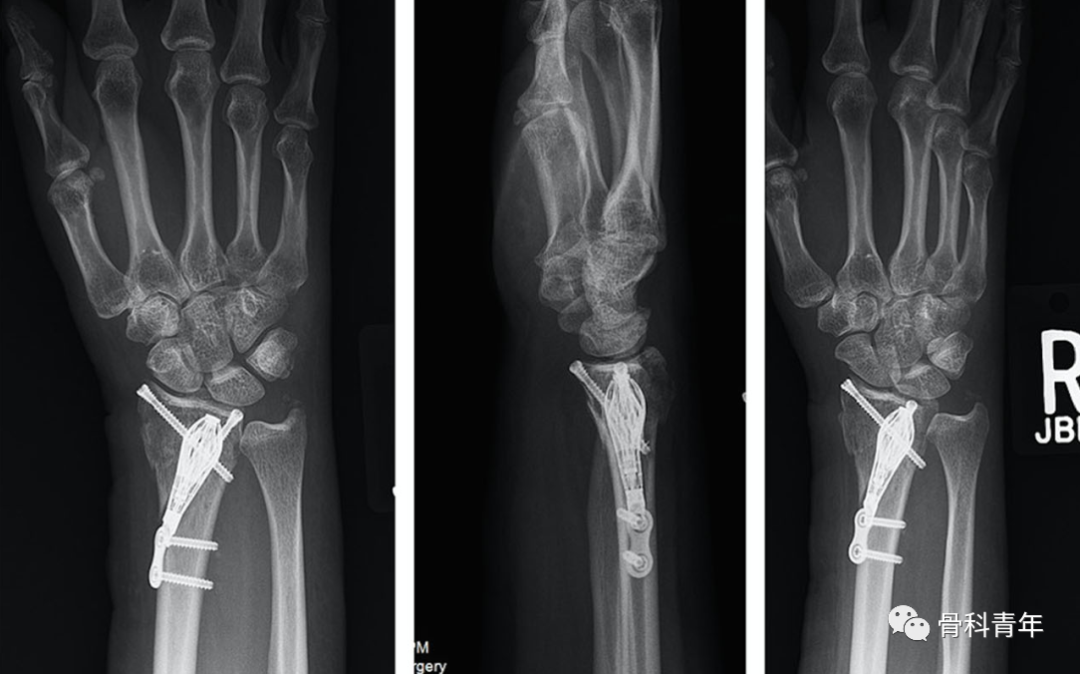

掌侧锁定加压接骨板(Volar locking compression plate,LCP)内固定是桡骨远端骨折治疗的金标准,但LCP并非对所有桡骨远端骨折均适用,如桡骨极远端骨折、背侧缘骨折、掌侧die-punch骨折等;同时,LCP钢板也具有一定的并发症发生率,包括旋前方肌损伤、骨折血运破坏、掌侧软组织激惹、背侧肌腱磨损等,同时对严重骨质疏松患者存在较高的内固定失效风险。

髓内钉技术广泛应用于长骨骨干骨折,闭合或有限切开复位有效降低医源性因素对血运的破坏,并具有良好的轴心固定生物学优势。桡骨远端髓内钉出现较晚,该技术适用于完全关节外骨折及简单的关节内骨折,对关节内粉碎骨折并不适用。

桡骨远端骨折髓内钉固定的前提是闭合复位效果满意,克氏针临时固定后,通过桡骨茎突开口,自腕背侧第1/2间室间隙进入。该技术存在潜在的损伤包括桡神经分支损伤,螺钉穿入下尺桡关节或桡腕关节等。